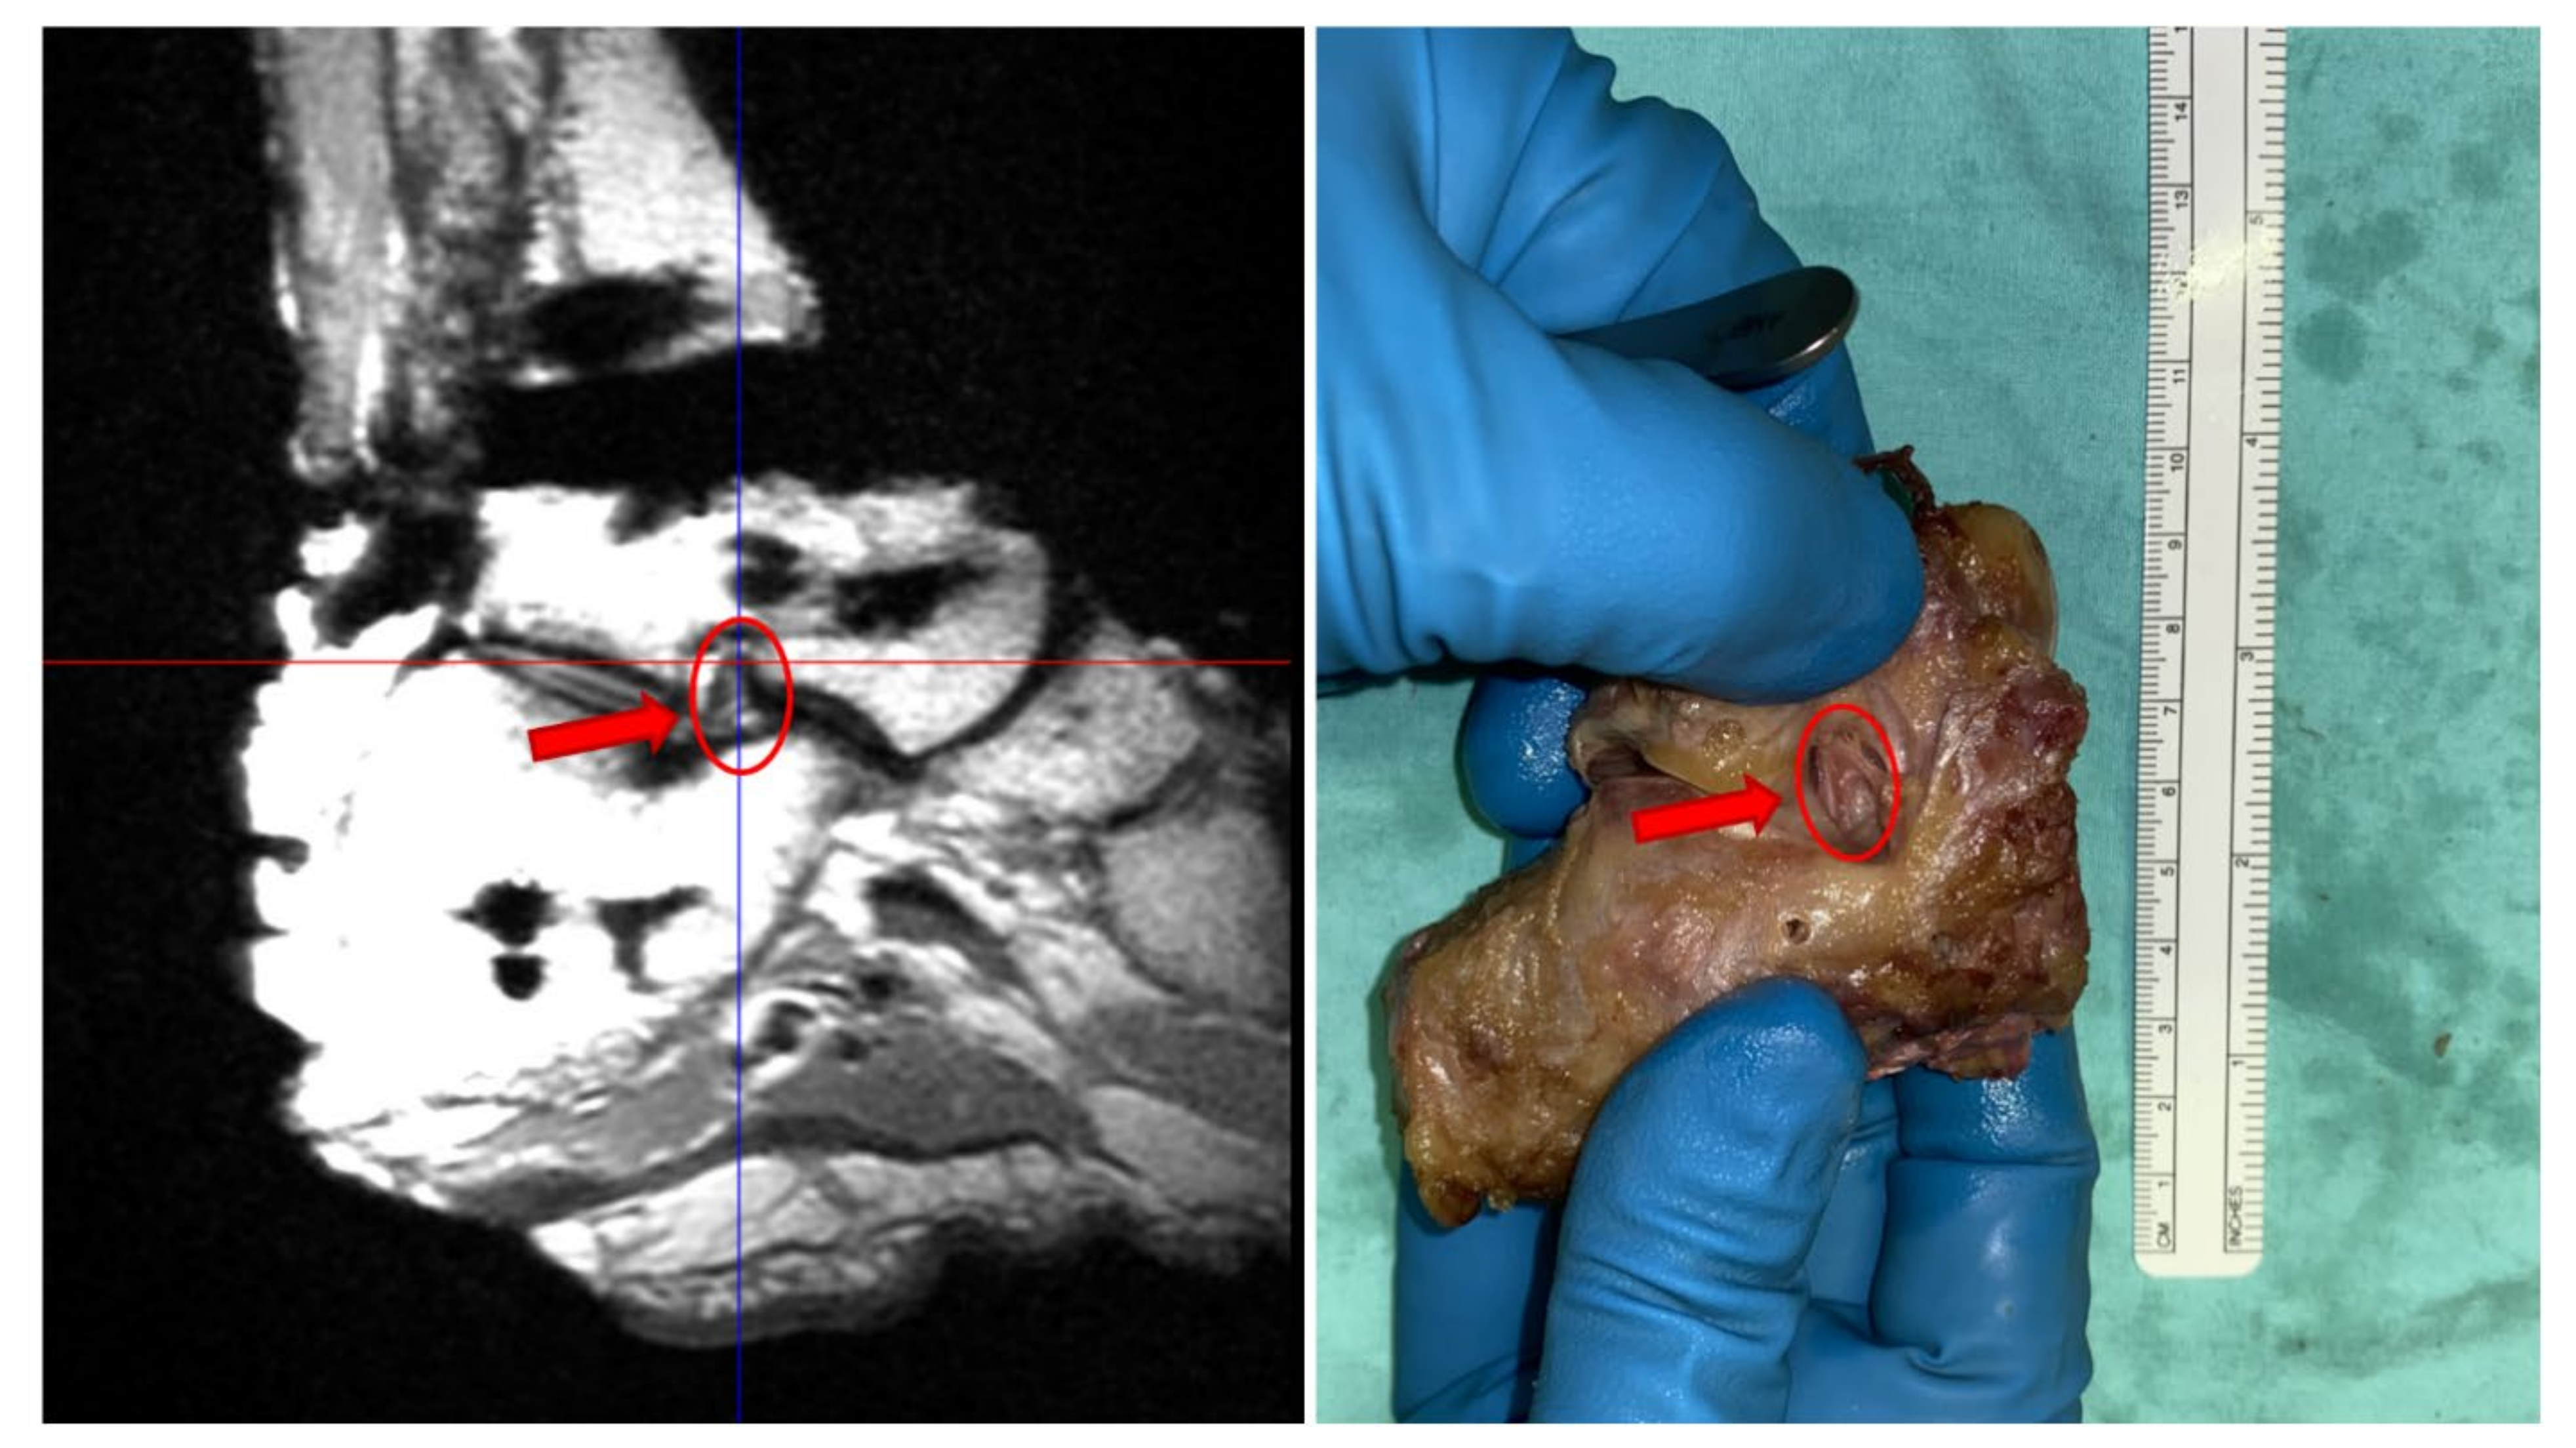

The ligaments attachment sites obtained from the 3.0 T MRI were better visualized than those from 1.5 T MRI and their locations were more consistent with those obtained from direct observations. All these three definition schemes provided similar data on the origin and insertion sites for the ankle complex ligaments, except for those of the subtalar joint, particularly for the ITCL. In the 1.5 T MRI, the ITCL consisted of two branches with a common insertion on the calcaneus (Figure 1A), which split in two distinguished origins on the lower surface of the talus (Figure 1B), one more lateral and the other more medial. In the 3.0 T MRI, the common origin was on the talus (Figure 1D) and then the two branches divided into a more anterior insertion area and a more posterior one on the lateral part of the lower surface of the calcaneus (Figure 1C). Overall, ligament attachment sites from the 3.0 T MRI were consistent with the direct observations from dissection (compare Figure 1E,F and Figure 2 left and right).

Figure 1. Maps of the subtalar ligaments from 1.5 T MRI (A,B), 3.0 T MRI (C,D), and from dissection (E,F): CL (yellow), ITCL (red). Origin areas on the bottom of the talus bone (B,D,F) and insertion areas on the top of the calcaneus bone (A,C,E).

Figure 2. ITCL from 3.0 T MRI (left) and from direct observation (right).